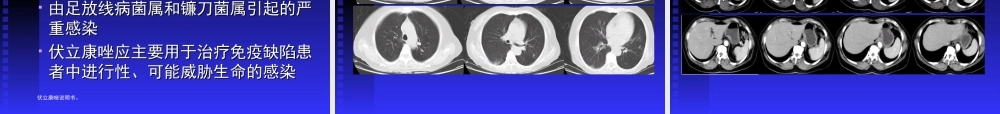

血液病患者真菌感染的经验治疗上海交通大学附属第一人民医院血液科上海交通大学附属第一人民医院血液科王椿王椿真菌感染逐渐增多真菌感染逐渐增多•诊断技术提高诊断技术提高•广谱抗生素的应用广谱抗生素的应用•患者年龄增高患者年龄增高•更多、更复杂的医疗干预措施更多、更复杂的医疗干预措施((如移植等如移植等))•高强度细胞毒性治疗的应用高强度细胞毒性治疗的应用•免疫抑制治疗的应用免疫抑制治疗的应用•其他病因死亡率的下降其他病因死亡率的下降系统性真菌感染的病原学主要致病菌为:主要致病菌为:念珠菌念珠菌((内源性条件致病菌内源性条件致病菌))曲霉菌曲霉菌((广泛存在于自然界和人体广泛存在于自然界和人体内内))隐球菌隐球菌((外源性致病菌外源性致病菌))组织胞浆菌组织胞浆菌侵袭性真菌感染的死亡率:美国真菌的感染死亡率逐年上升,90年之后,感染死亡有下降的趋势,与诊断措施的改进,和早期预防使用抗真菌药物有关。真菌感染率念珠菌白色念珠菌念珠菌病内脏真菌病中发病率最高内脏真菌病中发病率最高肺念珠菌病肺念珠菌病多继发其他呼吸道疾病,原发者少见。多继发其他呼吸道疾病,原发者少见。消化道念珠菌病消化道念珠菌病主要见于食道念珠菌病及念珠菌性肠炎主要见于食道念珠菌病及念珠菌性肠炎血性播散性念珠菌病血性播散性念珠菌病念珠菌经皮肤、肺部及肠道感染病灶侵入血念珠菌经皮肤、肺部及肠道感染病灶侵入血行行引起全身性系统性念珠菌病。引起全身性系统性念珠菌病。各种念珠菌感染所占的比例其他念珠菌1%热带念珠菌17%平滑念珠菌15%近平滑念珠菌9%克柔念珠菌4%白色念珠菌54%曲霉菌烟曲霉黄曲霉血液病患者真菌感染危险因素主要取决于三个因素的相互作用:主要取决于三个因素的相互作用:功能功能//解剖异常的存在,削弱了皮解剖异常的存在,削弱了皮肤黏膜对感染的屏障功能;肤黏膜对感染的屏障功能;过多地与潜在的真菌病原体接触;过多地与潜在的真菌病原体接触;免疫抑制状态。免疫抑制状态。功能/解剖异常的主要原因用于采血标本和输液的中心静脉插管的放置用于采血标本和输液的中心静脉插管的放置和化疗后黏膜炎,这两者都为念珠菌进入体和化疗后黏膜炎,这两者都为念珠菌进入体内提供了入口。内提供了入口。严重的皮肤损伤(如水的浸泡性损伤、血管严重的皮肤损伤(如水的浸泡性损伤、血管插管不当引起有害化学物质外渗到软组织而插管不当引起有害化学物质外渗到软组织...